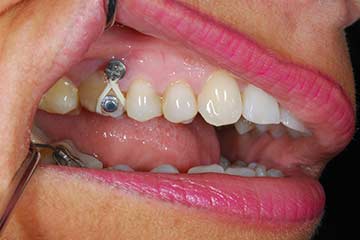

I denti irrecuperabili dell'arcata superiore ed inferiore del paziente di anni 65

sono stati sostituiti da 10 impianti, cioè protesi radicolari endo-ossee che sostengono le protesi fisse superiore ed inferiore.